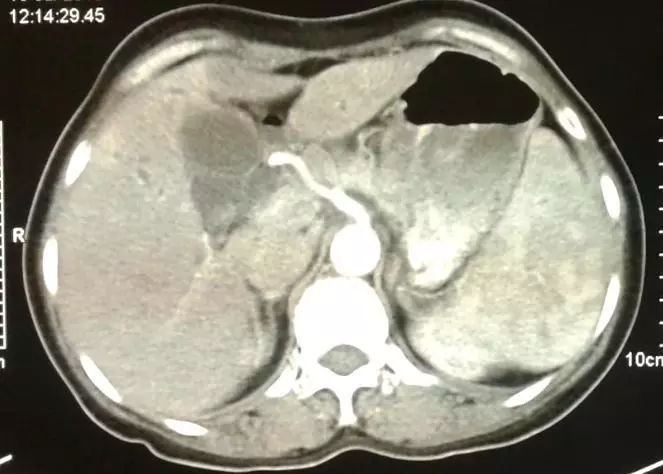

Ascaris lumbricoides感染方法简单安全,服用新鲜虫卵即可。成虫寄生于肠道和宿主竞争食物,从而达到减肥的目的,这种寄生在儿童身上可能导致malnutrition,但在成人身上的作用似乎十分有限。由于绝大多数Ascaris lumbricoides感染都是无症状的,所以被该虫寄生后宿主一般不甚痛苦。不过这玩意儿有个不好的习惯——喜欢钻,一旦钻到bile duct, appendix这种要命的地方,就会让人疼的满地打滚儿,并且大量成虫聚集于肠道还可以引起梗阻,大大降低了其食用的安全性。